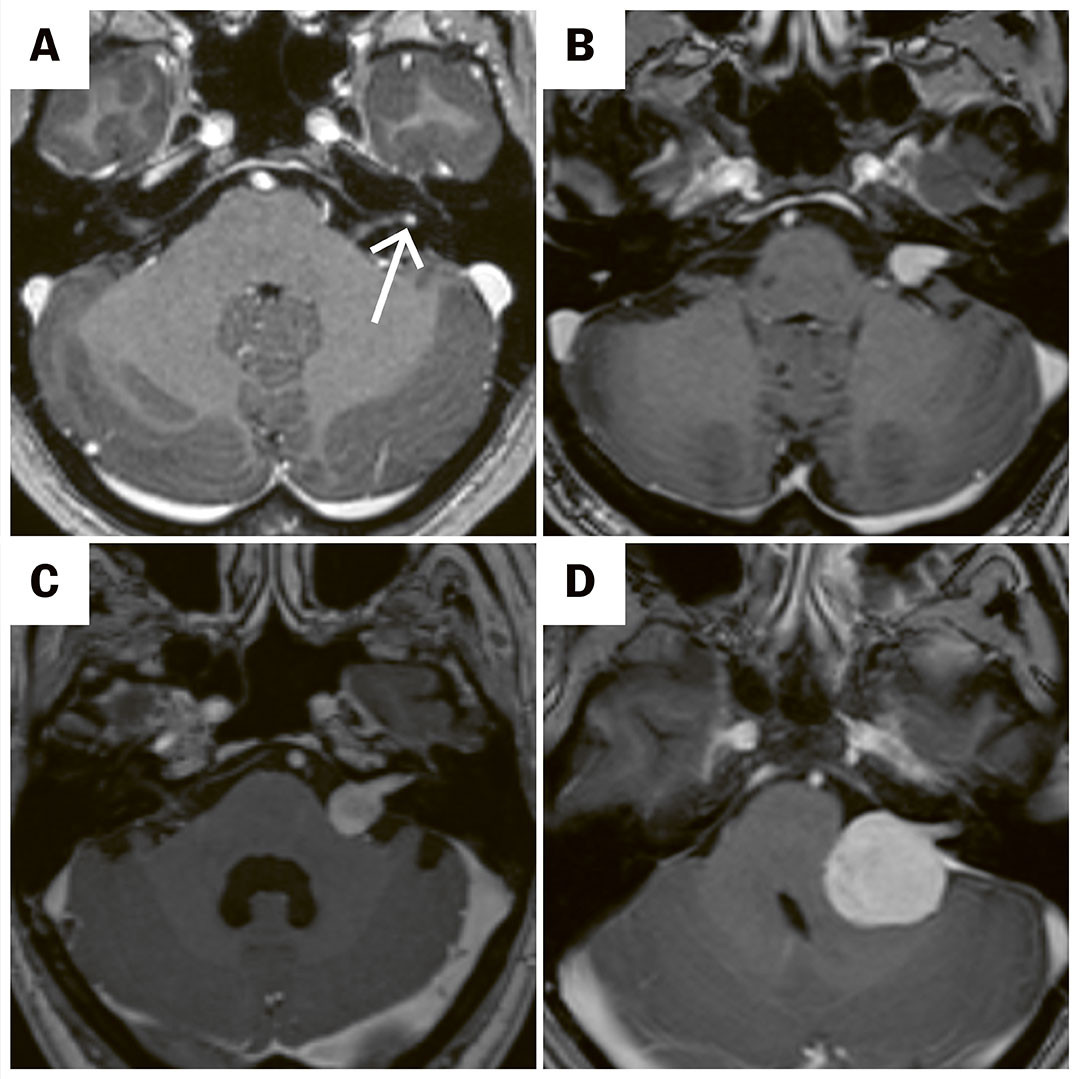

Pasienter med ensidig hørselstap som ikke kan forklares av annen årsak, skal utredes med MR av hodet. Typiske funn ved MR regnes som diagnostisk, og biopsi er ikke nødvendig for å stille diagnosen. Svulstens størrelse og påvirkning av omliggende nervevev graderes ut fra Koos' klassifikasjon, som går fra 1 (svulst utelukkende i indre øregang) til 4 (svulst som gir kompresjon av hjernestammen) (11) (figur 2). Størrelsen på svulsten blir vanligvis angitt etter måling av én eller flere diametere på MR-bildene. I senere år har man i økende grad benyttet volumetri for å bedre vurdere vekstmønsteret (12).